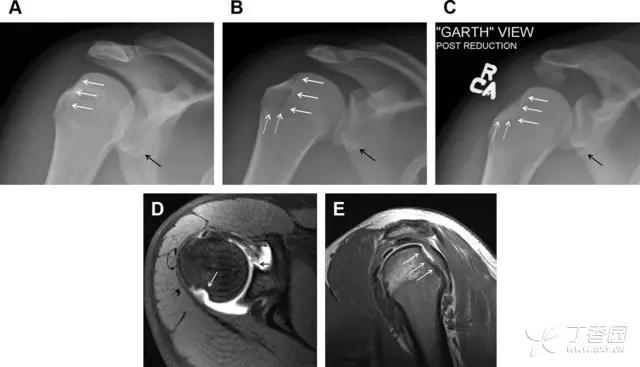

肩关节是最容易脱位的关节之一,肩关节脱位常伴随其它结构的损伤,如血管神经损伤、肩袖损伤、盂唇损伤、Bankart 损伤等。脱位本身诊断往往是明确的,容易被忽略的是其继发的伴随损伤。

需要仔细评估肱骨头、大结节、关节盂边缘、肩峰、喙突等结构。典型的 X 线投射角度包括:内旋位前后位片、外旋位前后位片(Grashey 位)、侧位(肩胛骨 Y 位)、腋位片以及改良腋位片。

图 6 肩关节前脱位伴有 Hill–Sachs 和 Bankart 损伤:(A~C)肱骨头后外侧撞击骨折,白色箭头所示为骨折的内侧边界;(A)内旋位前后位片,(B)「V」形压缩骨折的下边界(虚线短箭头),(C)Garth 位(轴向投影)示 Hill–Sachs 损伤(虚线和实线折箭头),特别是对骨性 Bankart 损伤的诊断有帮助。(D、E)MRI 进一步证实了损伤